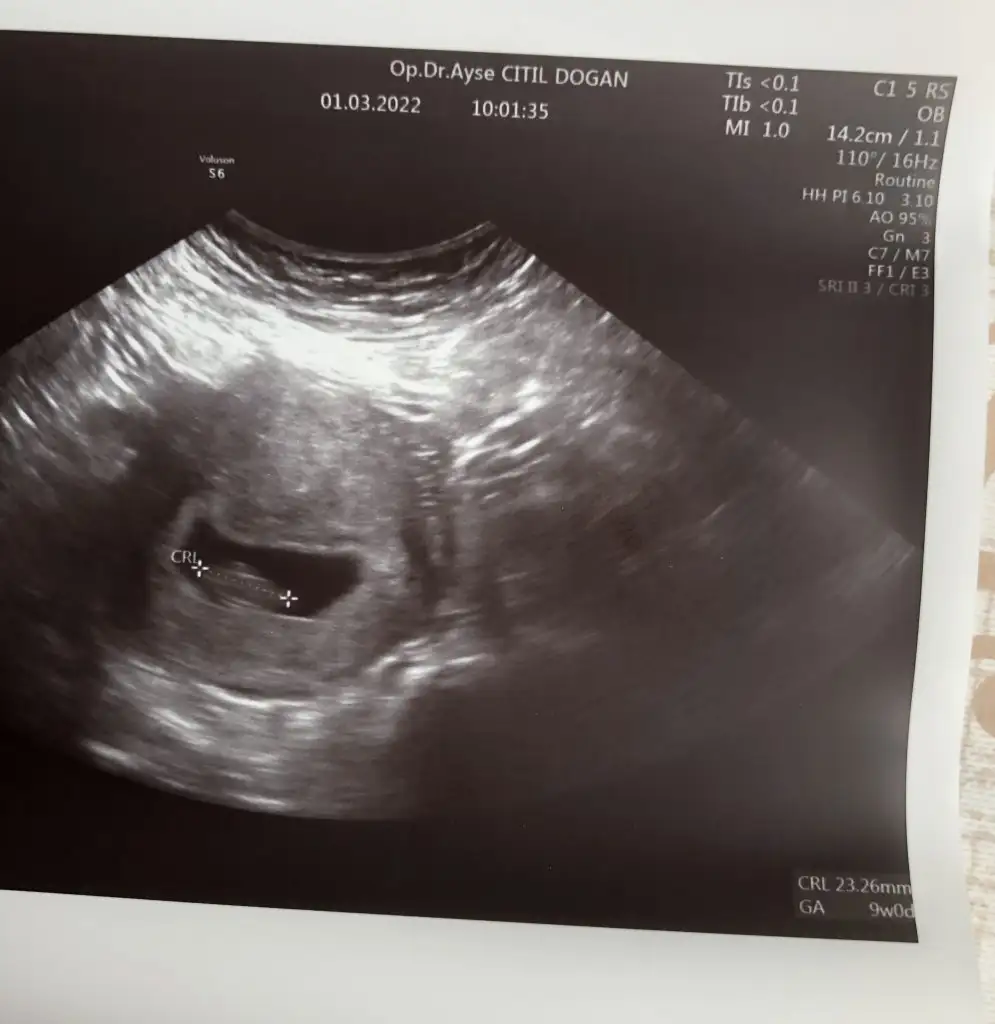

Arkadaşlar bugün doktora gittim. Karından ultrason baktı. 8+5 olmuş. Şükürler olsun iyi göründü. Korkuyorum diğer kaybımdan dolayı sağlıkla devam eder inş

uştrasonuna bakar mısınız? Cinsiyeti nedirEki Görüntüle 3016672 sizce?